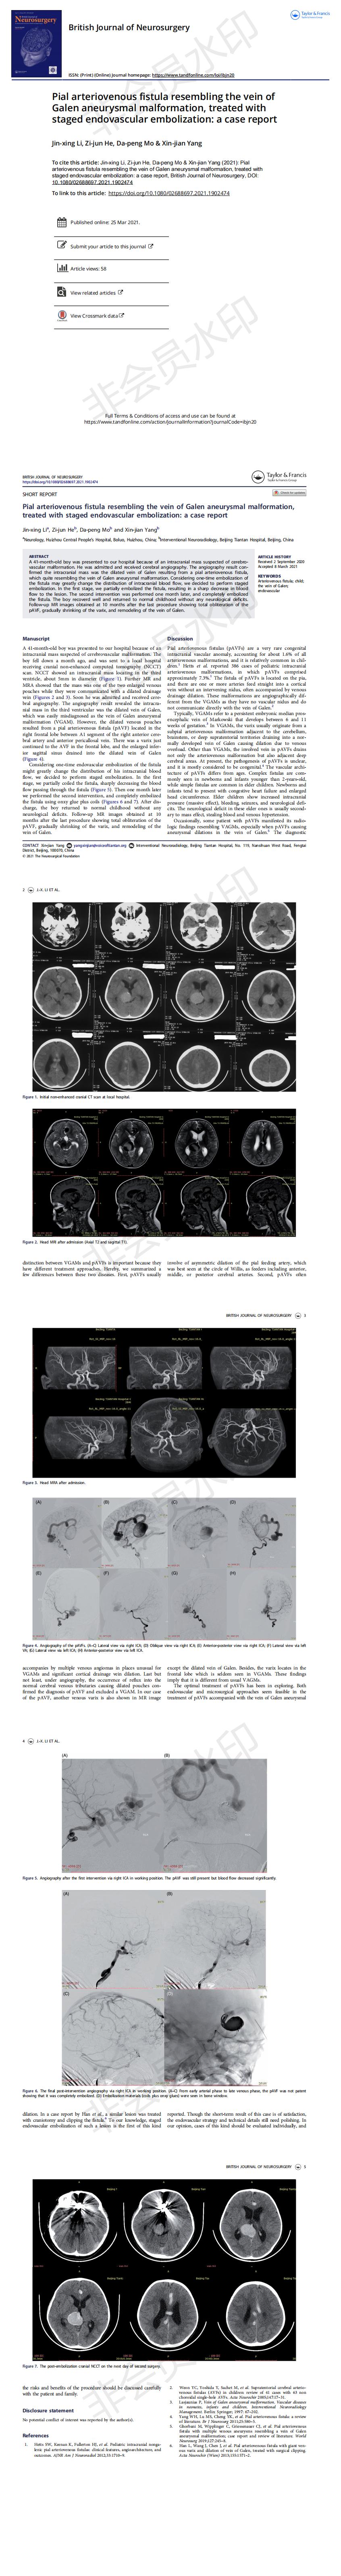

Pial arteriovenous fistula resembling the vein of Galen aneurysmal malformation, treated with staged endovascular embolization: a case report